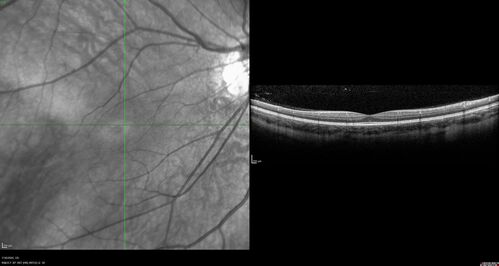

Familial Exudative Vitreoretinopathy - FEVR - Stage 1-b both eyes

She was born at term.   No family history of eye disease.

VA OD: Dcc20/25, VA OS: Dcc20/200+1 Ncc20/400

Anterior segment normal – clear lenses